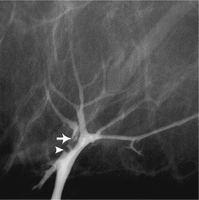

Akıntı gelen memebaşından süt kanalı içine az bir miktar kontrast madde verilerek, süt kanalının içini gösterecek şekilde mamografi filmi alınır.

Dolum defekti (koyu renk alan) genelde küçük bir kitleye işaret eder. Bunların çoğu papillomdur. Papillomların bazıları kansere dönüşme eğilimi gösterebildiğinden çıkarılmalıdır. Dolum defektlerinin yüzde 10’dan azını kanserler oluşturur.

Galaktografi sadece küçük kitleyi teşhis etmekle kalmaz, yerini de tespit ederek cerrahın kitleyi bulmasına yardımcı olur.

Bazen de akıntı nedeni süt kanalı ile ilişkili bir kist veya fibrokistik değişiklik alanıdır.